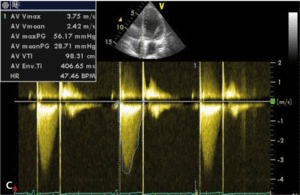

Rycina. Pomiar efektywnego pola ujścia protezy zastawkowej u chorej z wszczepioną sztuczną zastawką aortalną St Jude Medical 21A.

Ocenę funkcji wszczepionej zastawki umożliwia echokardiografia (ryc. 1). Ocena protezy zastawkowej wszczepionej w pozycję aortalną powinna uwzględniać analizę maksymalnej prędkości przepływu przez zastawkę (VmaxAo), średniego przezzastawkowego gradientu ciśnień (PmeanAo), całki prędkości przepływu w czasie przez zastawkę aortalną (VTIAo) i w drodze odpływu lewej komory (VTILVOT), indeksu prędkości przepływu proksymalnie do zastawki i prędkości na poziomie zastawki (DVIAo), efektywnego pola ujścia protezy zastawkowej (EOAAo), a także czasu akceleracji przepływu przez protezę zastawkową (ATAo) (tab. 1).

Liczne obserwacje i badania pozwoliły na opracowanie metody stosowanej do oceny wielkości wszczepianej zastawki w celu przeciwdziałania zjawisku niedopasowania [8-10]. Do ilościowej oceny stopnia niedopasowania zastawki aortalnej możemy posłużyć się tzw. indeksem efektywnego pola ujścia protezy zastawkowej aortalnej (EOAIAo), obliczanym z przekształconego wzoru ciągłości przepływu przez zastawkę aortalną:

W którym EOAAo oznacza efektywne pole ujścia protezy zastawkowej aortalnej, LVOTd – wymiar drogi odpływu lewej komory, VTILVOT – całkę prędkości przepływu w czasie w drodze odpływu lewej komory, a VTIAo – całkę prędkości przepływu w czasie przez zastawkę aortalną.